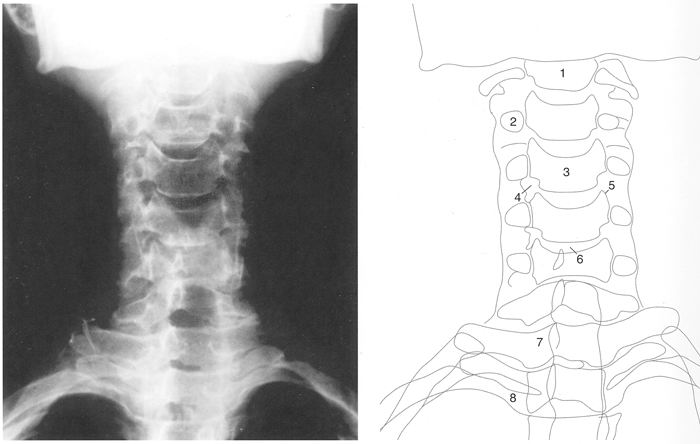

Commençons par le cervical, la suite viendra. Rachis cervical : radiographie, incidence antéro-postérieure

1. Axis

2. Processus transverse

3. Corps vertébral

4. Trou de conjugaison

5. Uncus

6. Disque intervétébralRachis cervical : radiographie, incidence de profil